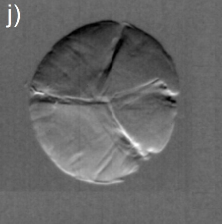

Dilute concentrations of precipitates without cores have also been observed, Figs. 3(e) and 3(f), as well as clinical cases of cataract with well-defined Y-sutures but with no distinct amounts of precipitates. In these cases, which correspond to 60% of the analyzed cases, there are significant scattering at the suture marks that can be generated either by local compaction of fiber cells or accumulation of precipitates along the marks, as for instance in Figs. 3(g) through 3(l). Refraction images show the extension of compaction areas while diffuse-scattering images can revel the presence or not of precipitates at the sutures. Absorption images (center of the analyzer window) provide essentially the same information of diffuse-scattering ones.